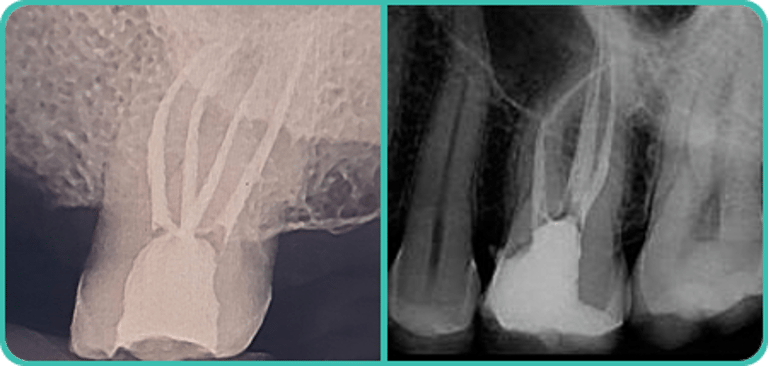

Procedimentos básicos:

Limpeza dental, remoção de tártaro, fluorterapia, pequenas restaurações, clareamento, tratamento de doenças gengivais, extrações, tratamento de traumas dentários e tratamento endodôntico (canal radicular).